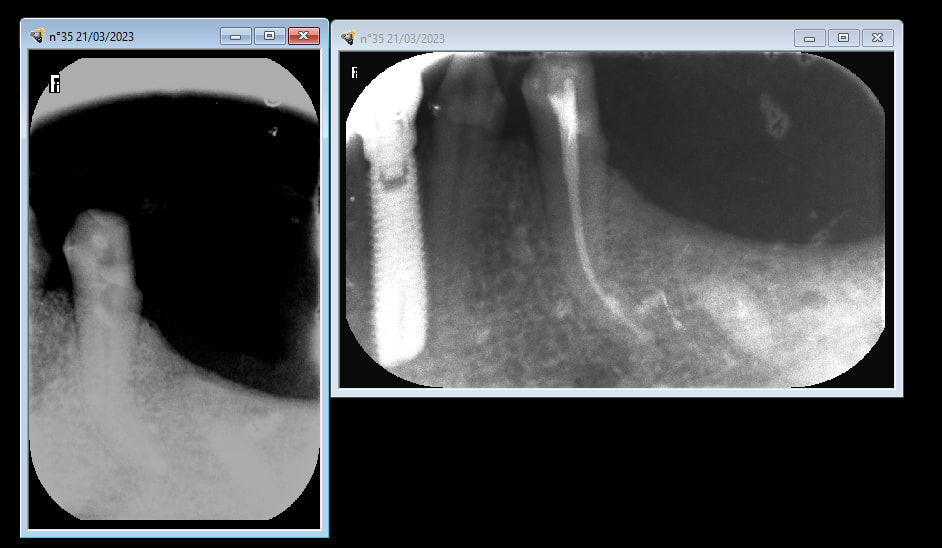

regardes le justicier inquiet , toi qui aimes voir les radios , je viens de faire une endo cet aprem .

et je t ai même pris la radio avant , chose que je ne fais pas souvent ( puisqu elles ne me servent à rien tellement elles sont pourries mes radios ) , je l ai faite rien que pour toi , pour ne pas que tu crois que je te sorte encore une " endo de ma vie " comme tu as su me le dire la dernière fois , la radio d' avant étant datée d aujourd'hui .

bon le canal est très fin , tordu et profond , et tu crois que ça m inquiète quand au choix de la pétale ou de je ne sais quoi ? :-))